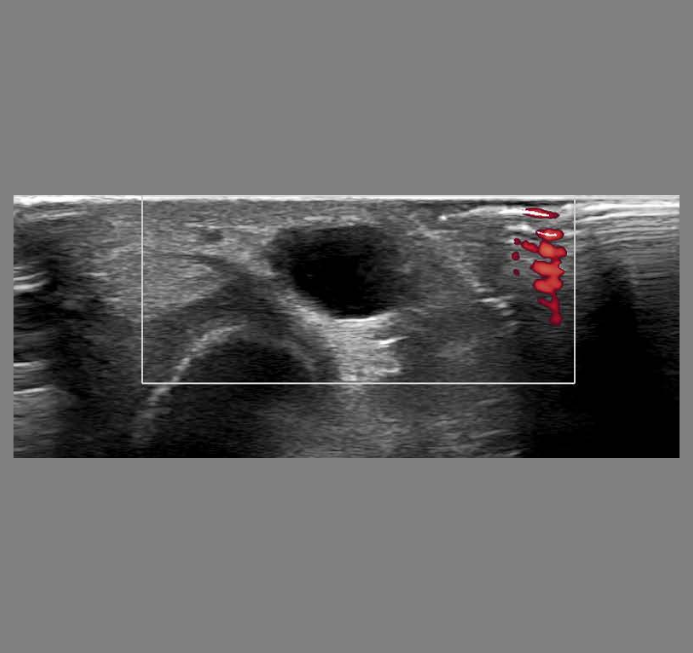

Depending on individual needs, imaging is available as part of the initial investigation. These include MRI, X-rays, CT and Ultrasound scans. Consultations are available to discuss this further.